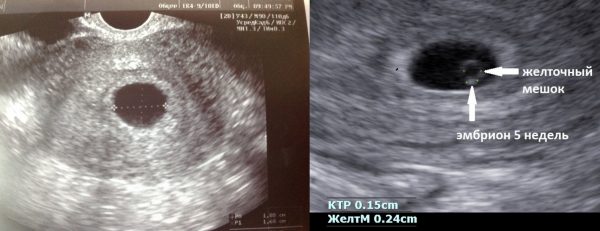

УЗД-діагностика

Для уточнення діагнозу лікар призначить УЗД і тільки потім зробить остаточний висновок.

При проведенні УЗД-діагностики можуть бути виявлені:

- анембріонія - плодове яйце менших розмірів і не візуалізується;

- ретрохоріальная гематома, або скупчення крові усередині матки, через що відшарувалися оболонок і відторгнутого ембріона;

- відсутність серцебиття у візуалізується всередині плодового яйця ембріона;

- змащені контури деформованого плодового яйця;

- відставання розмірів матки від норм.